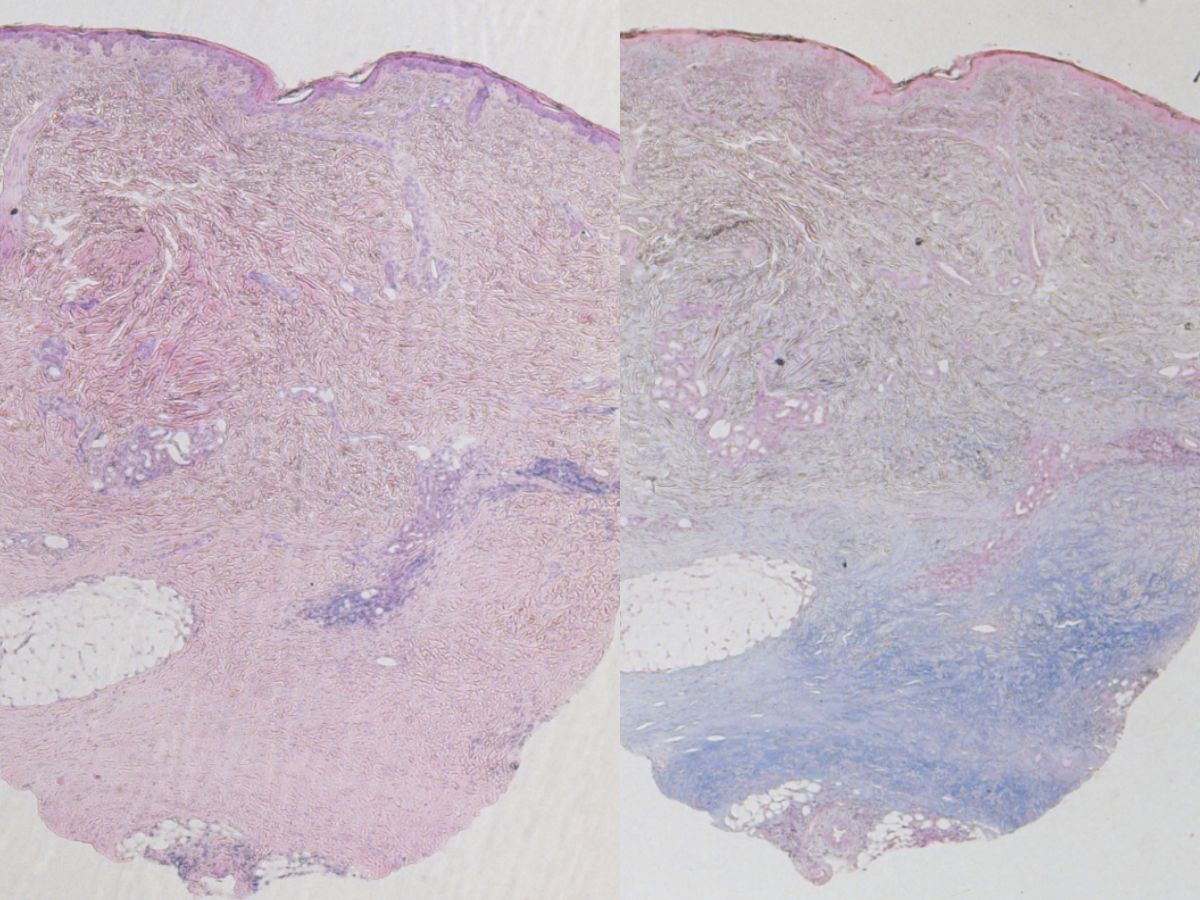

Histopathologisch onderzoek:Epidermis zonder afwijkingen.

De reticulaire dermis is sterk verbreed, met name in de diepere delen door een

toename van brede collageen bundels die vrij dicht opeen gepakt zijn. Er is

collageentoename ook in de interlobulaire vetsepta in de panniculus met enig

verlies van vetweefsel rond de adnexen. Er zijn ophopingen van grijzig homogeen

materiaal tussen het collageen welke blauw aankleurt in de Acian Blue kleuring.

Verder een matig tot uitgesproken ontstekingsinfiltraat opgebouwd m.n. uit lymfocyten

en soms eosinofiele granulocyten perivasculair en in het subcutane vetweefsel,

dit onderscheidt morphea profunda van de ‘gewone’ morphea.